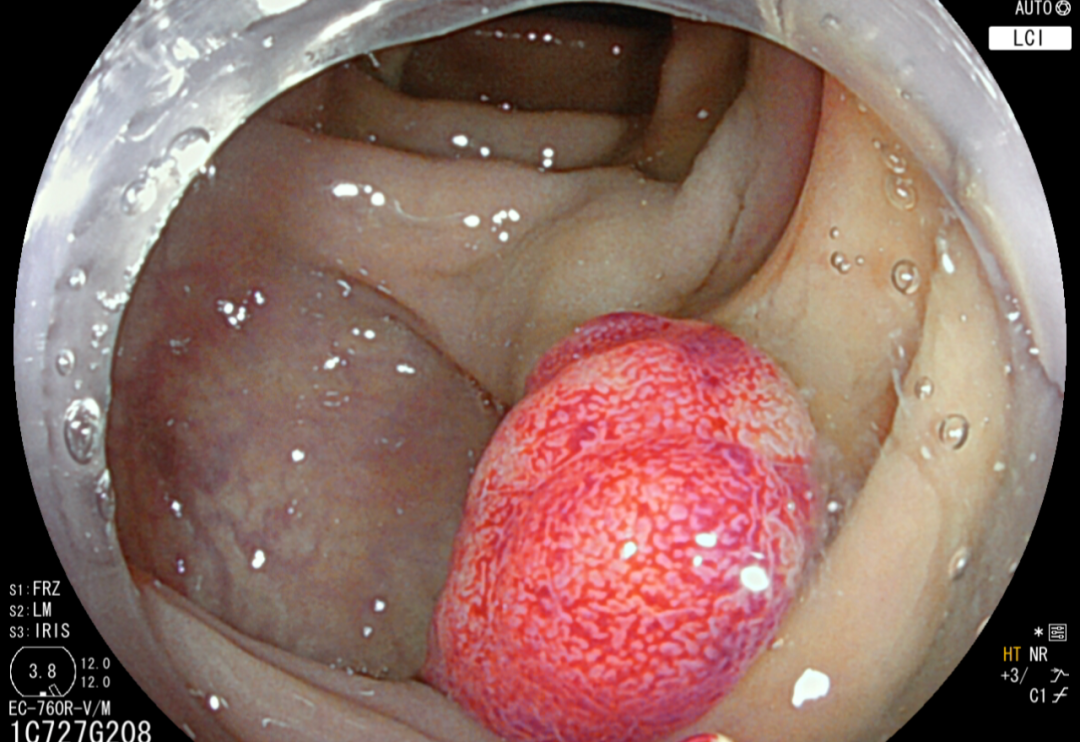

于是他前去西南医科大学从属中医病院就诊,肛肠科主任李五生传授接诊后,为其完美肠镜提醒“直肠肿瘤”,病理搜检究竟为:直肠黏膜腺癌。同时认识到李明有肠癌家眷史,曾有亲人因直肠癌作古,于是李五生传授团队立刻为其开展了“腹腔镜下直肠癌根治术”,李明几日后便康复出院。

直肠癌属于大肠癌的一种,是乙状结肠与直肠接壤处至齿状线之间的癌,即发源于直肠和肛管的癌瘤统称为直肠癌,是消化道常见的恶性肿瘤之一。早期直肠癌的预后对照好,若是经由根治性手术切除,患者能够历久存活。

科室对结直肠良恶性肿瘤、肠道息肉、盆底疾病、盆腔肌肉神经、耻骨直肠肌综合症、盆底肌综合症、盆底神经综合症、直肠脱垂、直肠前突、肛门括约肌失驰缓、肛门失禁、慢性便秘、结肠功能杂乱的搜检诊断和治疗,具有奇特优势和疗效。科室开展了内痔的打针及套扎(RPH)、夹杂痔外剥内扎、肛周脓肿根治术、高位复杂肛瘘根治术、直肠脱垂手术(LVMR、Altemeier、Delorme)、直肠..瘘修补术、藏毛窦Limberg手术,肛裂切除+内括约肌松解术、肛门狭小、结肠癌根治术、直肠癌根治术、低位、超低位直肠癌保肛手术等诊治工作,大肠癌首要接纳腹腔镜微创手艺,具有创伤小、疼痛小、恢复快等长处。科室还拥有最新的宾得、富士结肠镜,首要开展无痛肠镜搜检、肠镜下息肉电凝、圈套、EMR(内镜下粘膜切除术)及早期肿瘤ESD(内镜下粘膜剥离术)治疗,下消化道出血内镜止血术、狭小扩张等手艺。